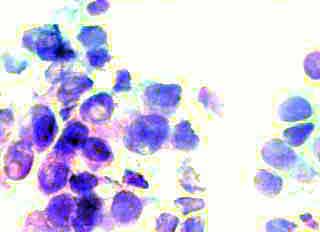

Κατόπιν αυτού, παρακέντηση λεπτής βελόνης κάτω από υπερηχογραφικό έλεγχο και άμεση χρώση παρασκευάσματος κατά Papanicolaou. Κυτταρολογικώς χαρακτηριστικές εικόνες νεοπλασίας.

Η εξέταση μετά από μικρή μερική μαστεκτομή, κατέδειξε λοβικό Ca μαστού με ελεύθερους τους μασχαλιαίους αδένες.